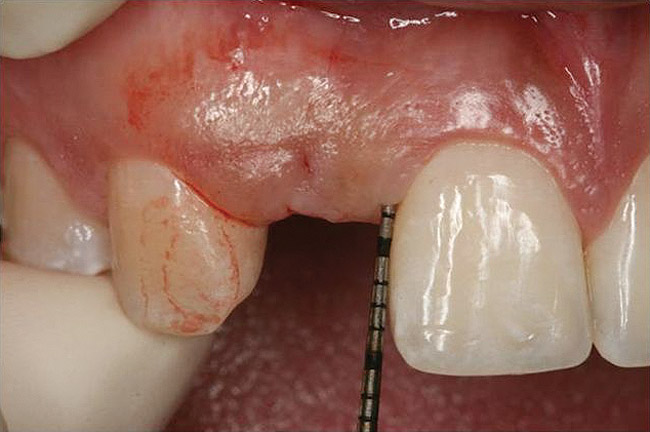

Figure 6  Characterization of the interproximal bone and tooth contacts: A periapical radiograph assists in measuring the distance from bone crest to the adjacent tooth contact points for missing tooth No. 8. The mesial bone crest to the adjacent tooth contact distance is < 5 mm, while the distal bone crest to adjacent tooth contact distance is > 6 mm (Fig 4). One-year following implant placement, conservation of these dimensions is revealed (Fig 5). The clinical photograph (Fig 6) of the lateral incisor adjacent to tooth No. 8 implant crown demonstrates that the absence of distal interproximal (papilla) fill related to the observed bone crest to contact distance exceeds 6 mm.

Figure 6

Figure 4  Characterization of the interproximal bone and tooth contacts: A periapical radiograph assists in measuring the distance from bone crest to the adjacent tooth contact points for missing tooth No. 8. The mesial bone crest to the adjacent tooth contact distance is < 5 mm, while the distal bone crest to adjacent tooth contact distance is > 6 mm (Fig 4). One-year following implant placement, conservation of these dimensions is revealed (Fig 5). The clinical photograph (Fig 6) of the lateral incisor adjacent to tooth No. 8 implant crown demonstrates that the absence of distal interproximal (papilla) fill related to the observed bone crest to contact distance exceeds 6 mm.

Figure 5  Characterization of the interproximal bone and tooth contacts: A periapical radiograph assists in measuring the distance from bone crest to the adjacent tooth contact points for missing tooth No. 8. The mesial bone crest to the adjacent tooth contact distance is < 5 mm, while the distal bone crest to adjacent tooth contact distance is > 6 mm (Fig 4). One-year following implant placement, conservation of these dimensions is revealed (Fig 5). The clinical photograph (Fig 6) of the lateral incisor adjacent to tooth No. 8 implant crown demonstrates that the absence of distal interproximal (papilla) fill related to the observed bone crest to contact distance exceeds 6 mm.